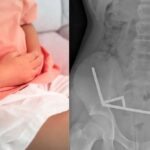

Рендгенската снимка го шокираше светот, 100 магнети формираа синџир во стомакот